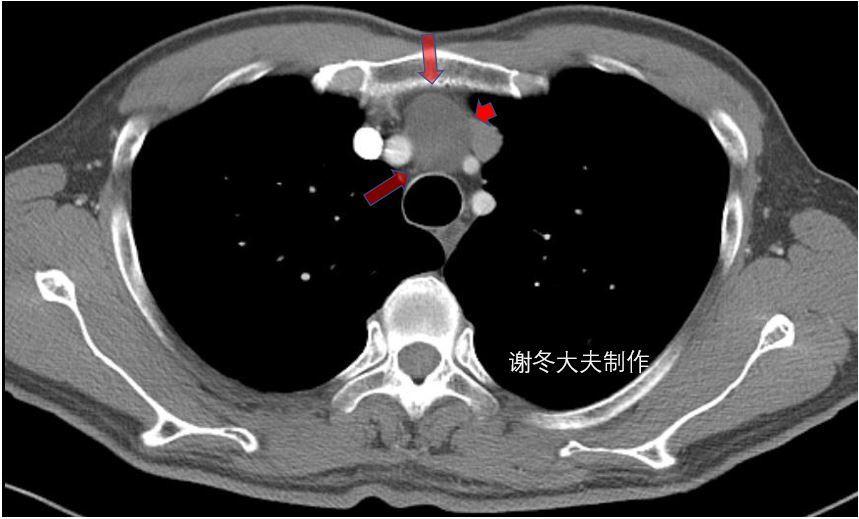

2.侵袭性胸腺瘤

侵袭性胸腺瘤明确的CT征象:纵隔结构的包绕,直接侵犯中心静脉、心包或胸膜种植转移和晚期发生的跨膈肌扩散。

侵犯上腔静脉,伴有双侧胸水